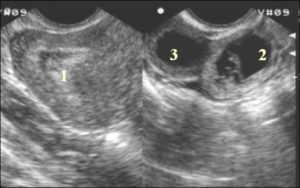

- Желтое тело можно обнаружить в виде округлого мешочка неоднородной структуры, который располагается обычно с одной стороны яичника.

- Желтое тело обязательно должно быть немного приподнято над уровнем яичника. Если на ультразвуке отчетливо не видно выделение округлого мешочка, а беременность как факт зафиксирована – это может быть плохим признаком угрозы выкидыша из-за причины недостатка гормона беременности в организме.

Его размеры (мм) в различных клинических ситуациях будут отличаться:

- 12- 15 Сразу после освобождения яйцеклетки говорит о его наличии. В конце менструального цикла — об отсутствии беременности и обратном развитии желтого тела.

- 18-20-24 Спустя неделю после овуляции сигнализирует о том, что выход яйцеклетки произошел и организм готов к выращиванию плодного яйца (даже если зачатие не произошло).

- 30- 40 Киста желтого тела.

- 20-30 Нормально протекающая беременность.